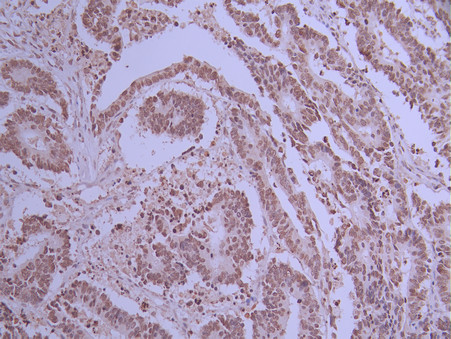

IHC image of CSB-RA098504A0HU diluted at 1:100 and staining in paraffin-embedded human colorectal cancer performed on a Leica BondTM system. After dewaxing and hydration, antigen retrieval was mediated by high pressure in a citrate buffer (pH 6.0). Section was blocked with 10% normal goat serum 30min at RT. Then primary antibody (1% BSA) was incubated at 4°C overnight. The primary is detected by a Goat anti-rabbit polymer IgG labeled by HRP and visualized using 0.05% DAB.